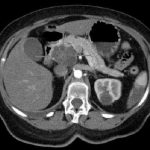

(Cancro del polmone-Immagine: un nuovo studio condotto dalla Washington University School of Medicine di St. Louis mostra che il nuovo farmaco Sotorasib avvantaggia molti pazienti con carcinoma polmonare non a piccole cellule con una specifica mutazione nel gene KRAS. In un piccolo sottogruppo di pazienti, il farmaco ha eliminato tutte le prove dei tumori. La foto a sinistra è una scansione che mostra un tumore al polmone (cerchio giallo) che si è diffuso al muscolo. L’immagine a destra mostra lo stesso paziente dopo due mesi di terapia con Sotorasib. Nessun tumore è visibile nel cerchio giallo a destra. Credito: Siddhartha Devarakonda).